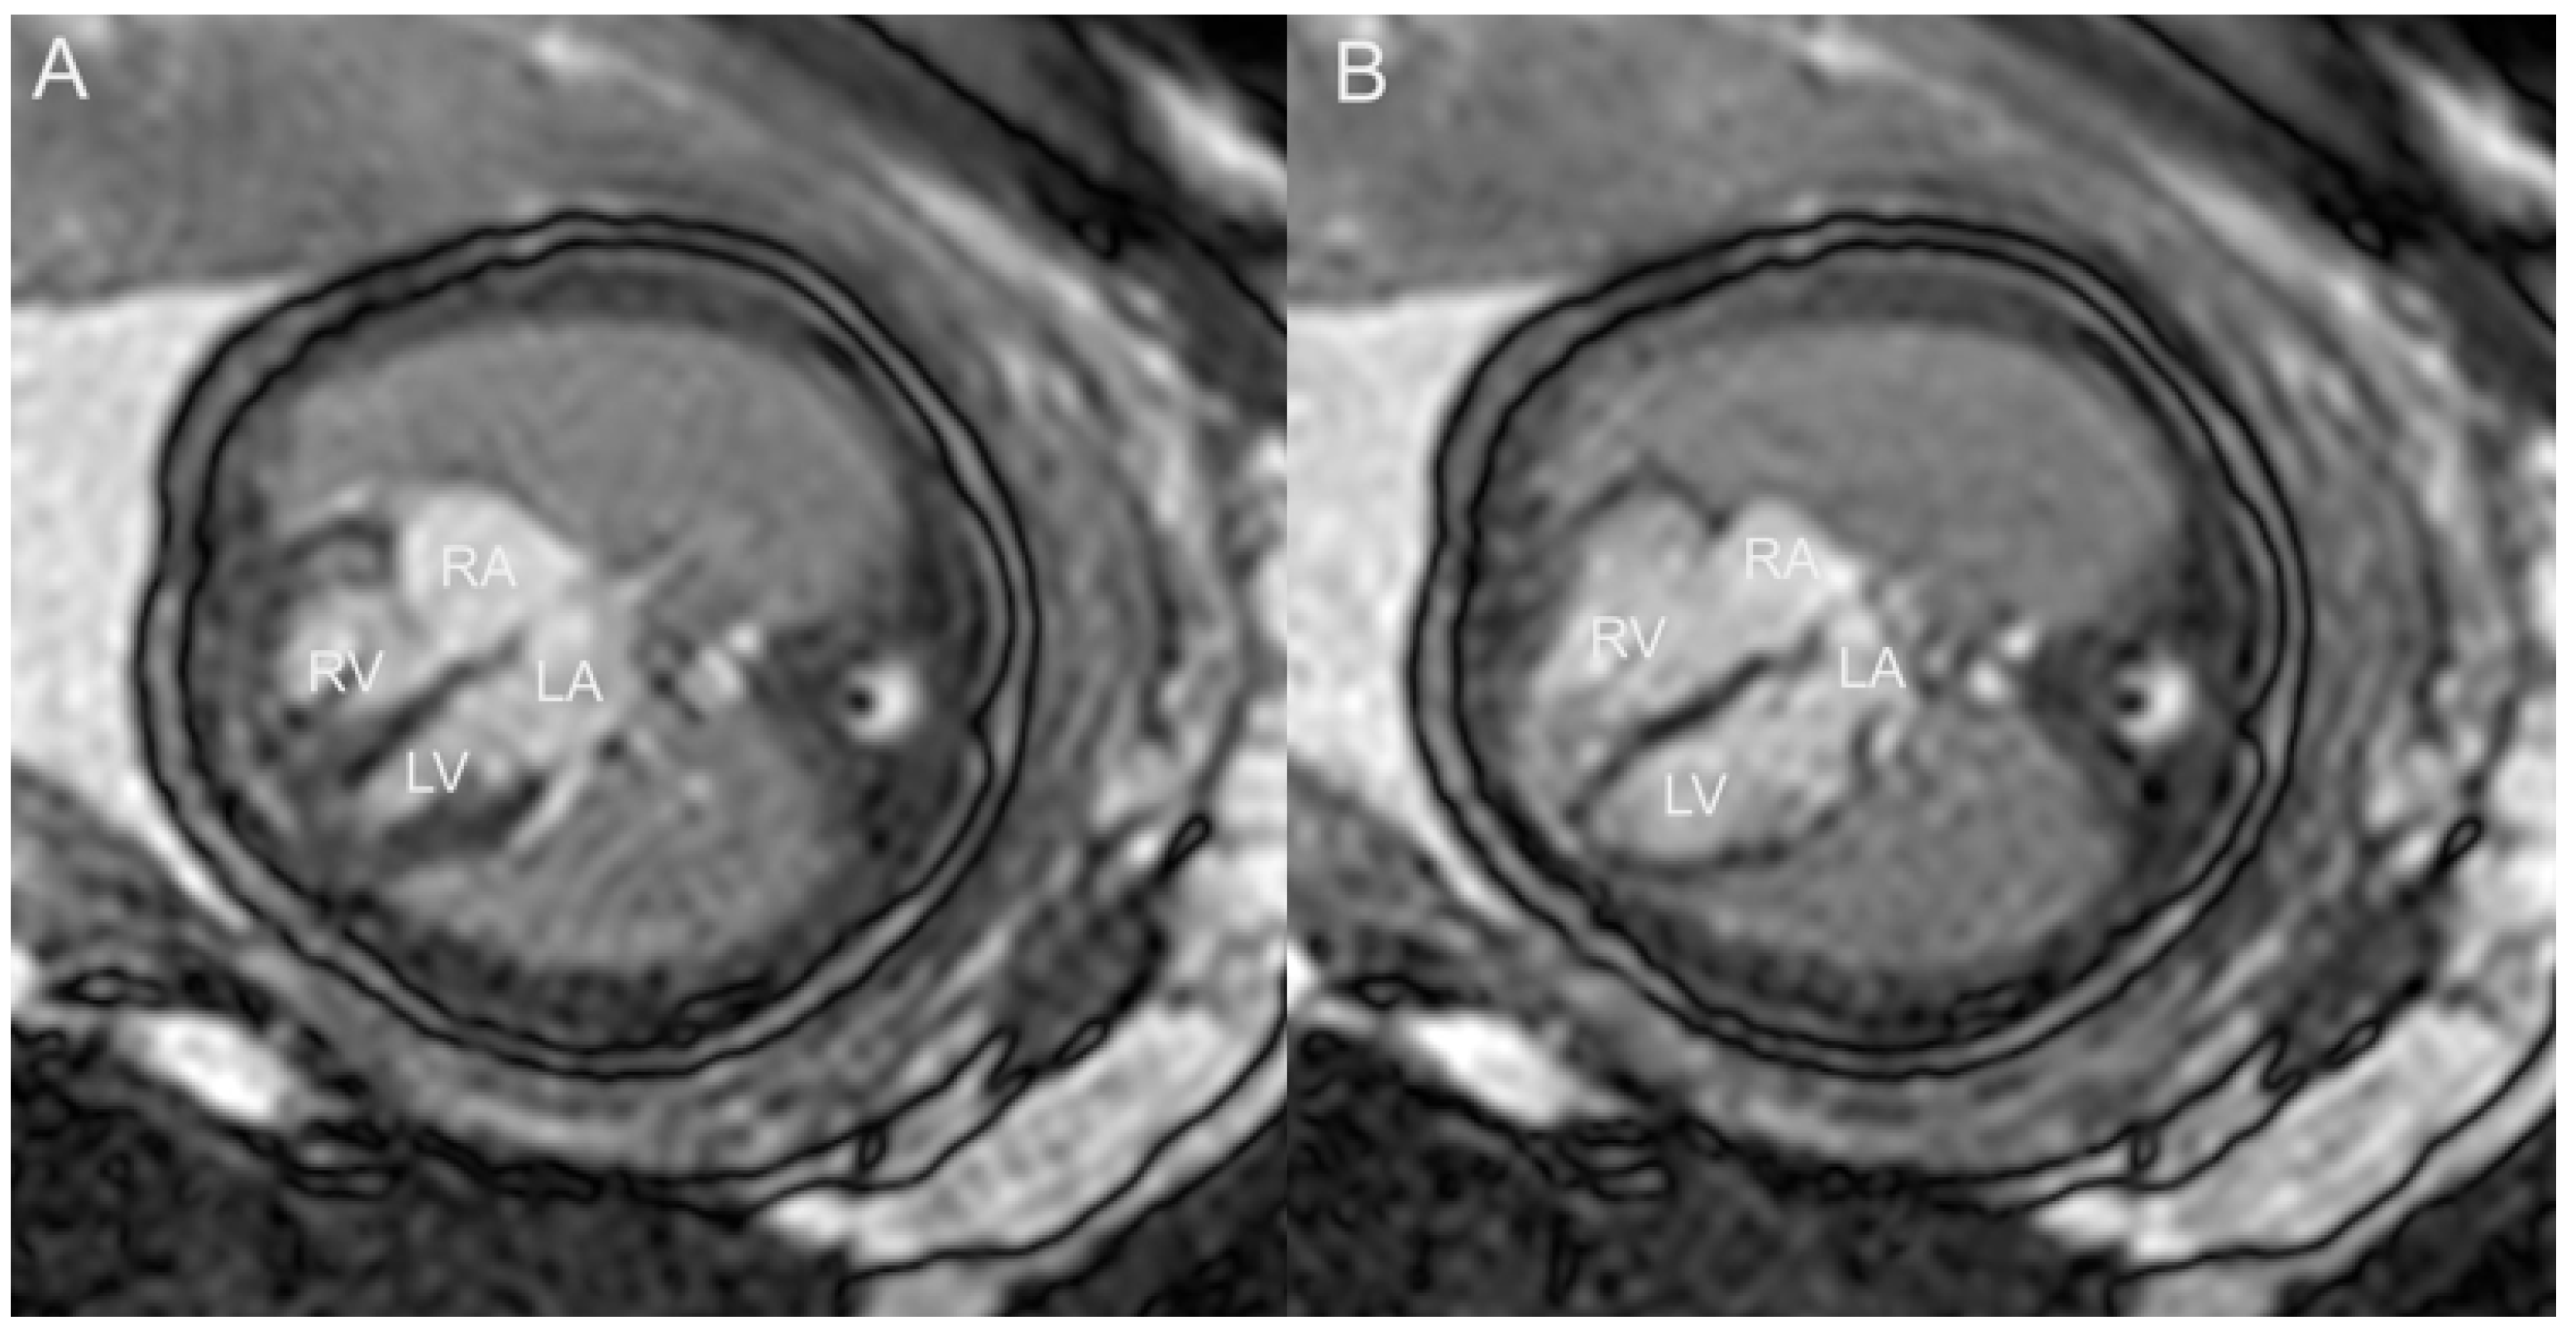

- Rubert NC, Jategaonkar G, Plasencia JD, Lindblade CL, Bardo DME, Goncalves LF. Four-dimensional fetal cardiac imaging in a cohort of fetuses with suspected congenital heart disease. Pediatr Radiol. 2023, 53, 198–209.